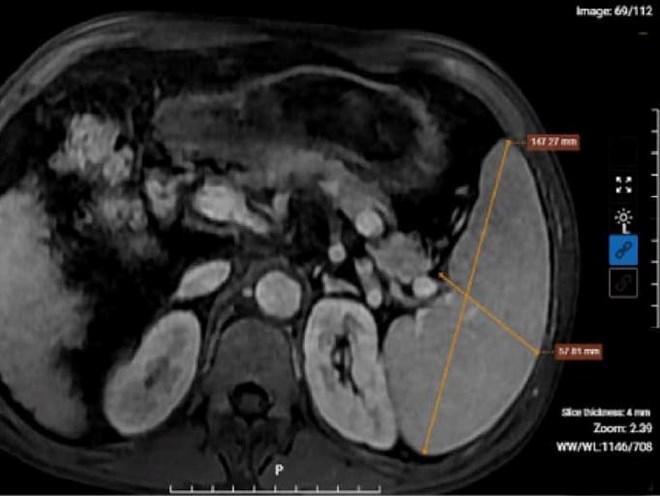

Kết quả chụp MRI của bệnh nhân nghiện rượu cho thấy hình ảnh xơ gan lách to, dịch bao quanh gan. Ảnh: BVCC

Sau khi thăm khám lâm sàng và thực hiện các xét nghiệm, chẩn đoán hình ảnh cần thiết, kết quả chỉ số men gan AST, ALT, Bilirubin trong máu của bệnh nhân tăng ở mức báo động, cùng tình trạng xơ gan mất bù, kèm theo dịch ổ bụng. Đồng thời, kết quả xét nghiệm của bệnh nhân còn phát hiện dương tính với viêm gan B. Bác sĩ đưa ra chẩn đoán xác định bệnh nhân mắc xơ gan mất bù kèm viêm gan B mạn tính.